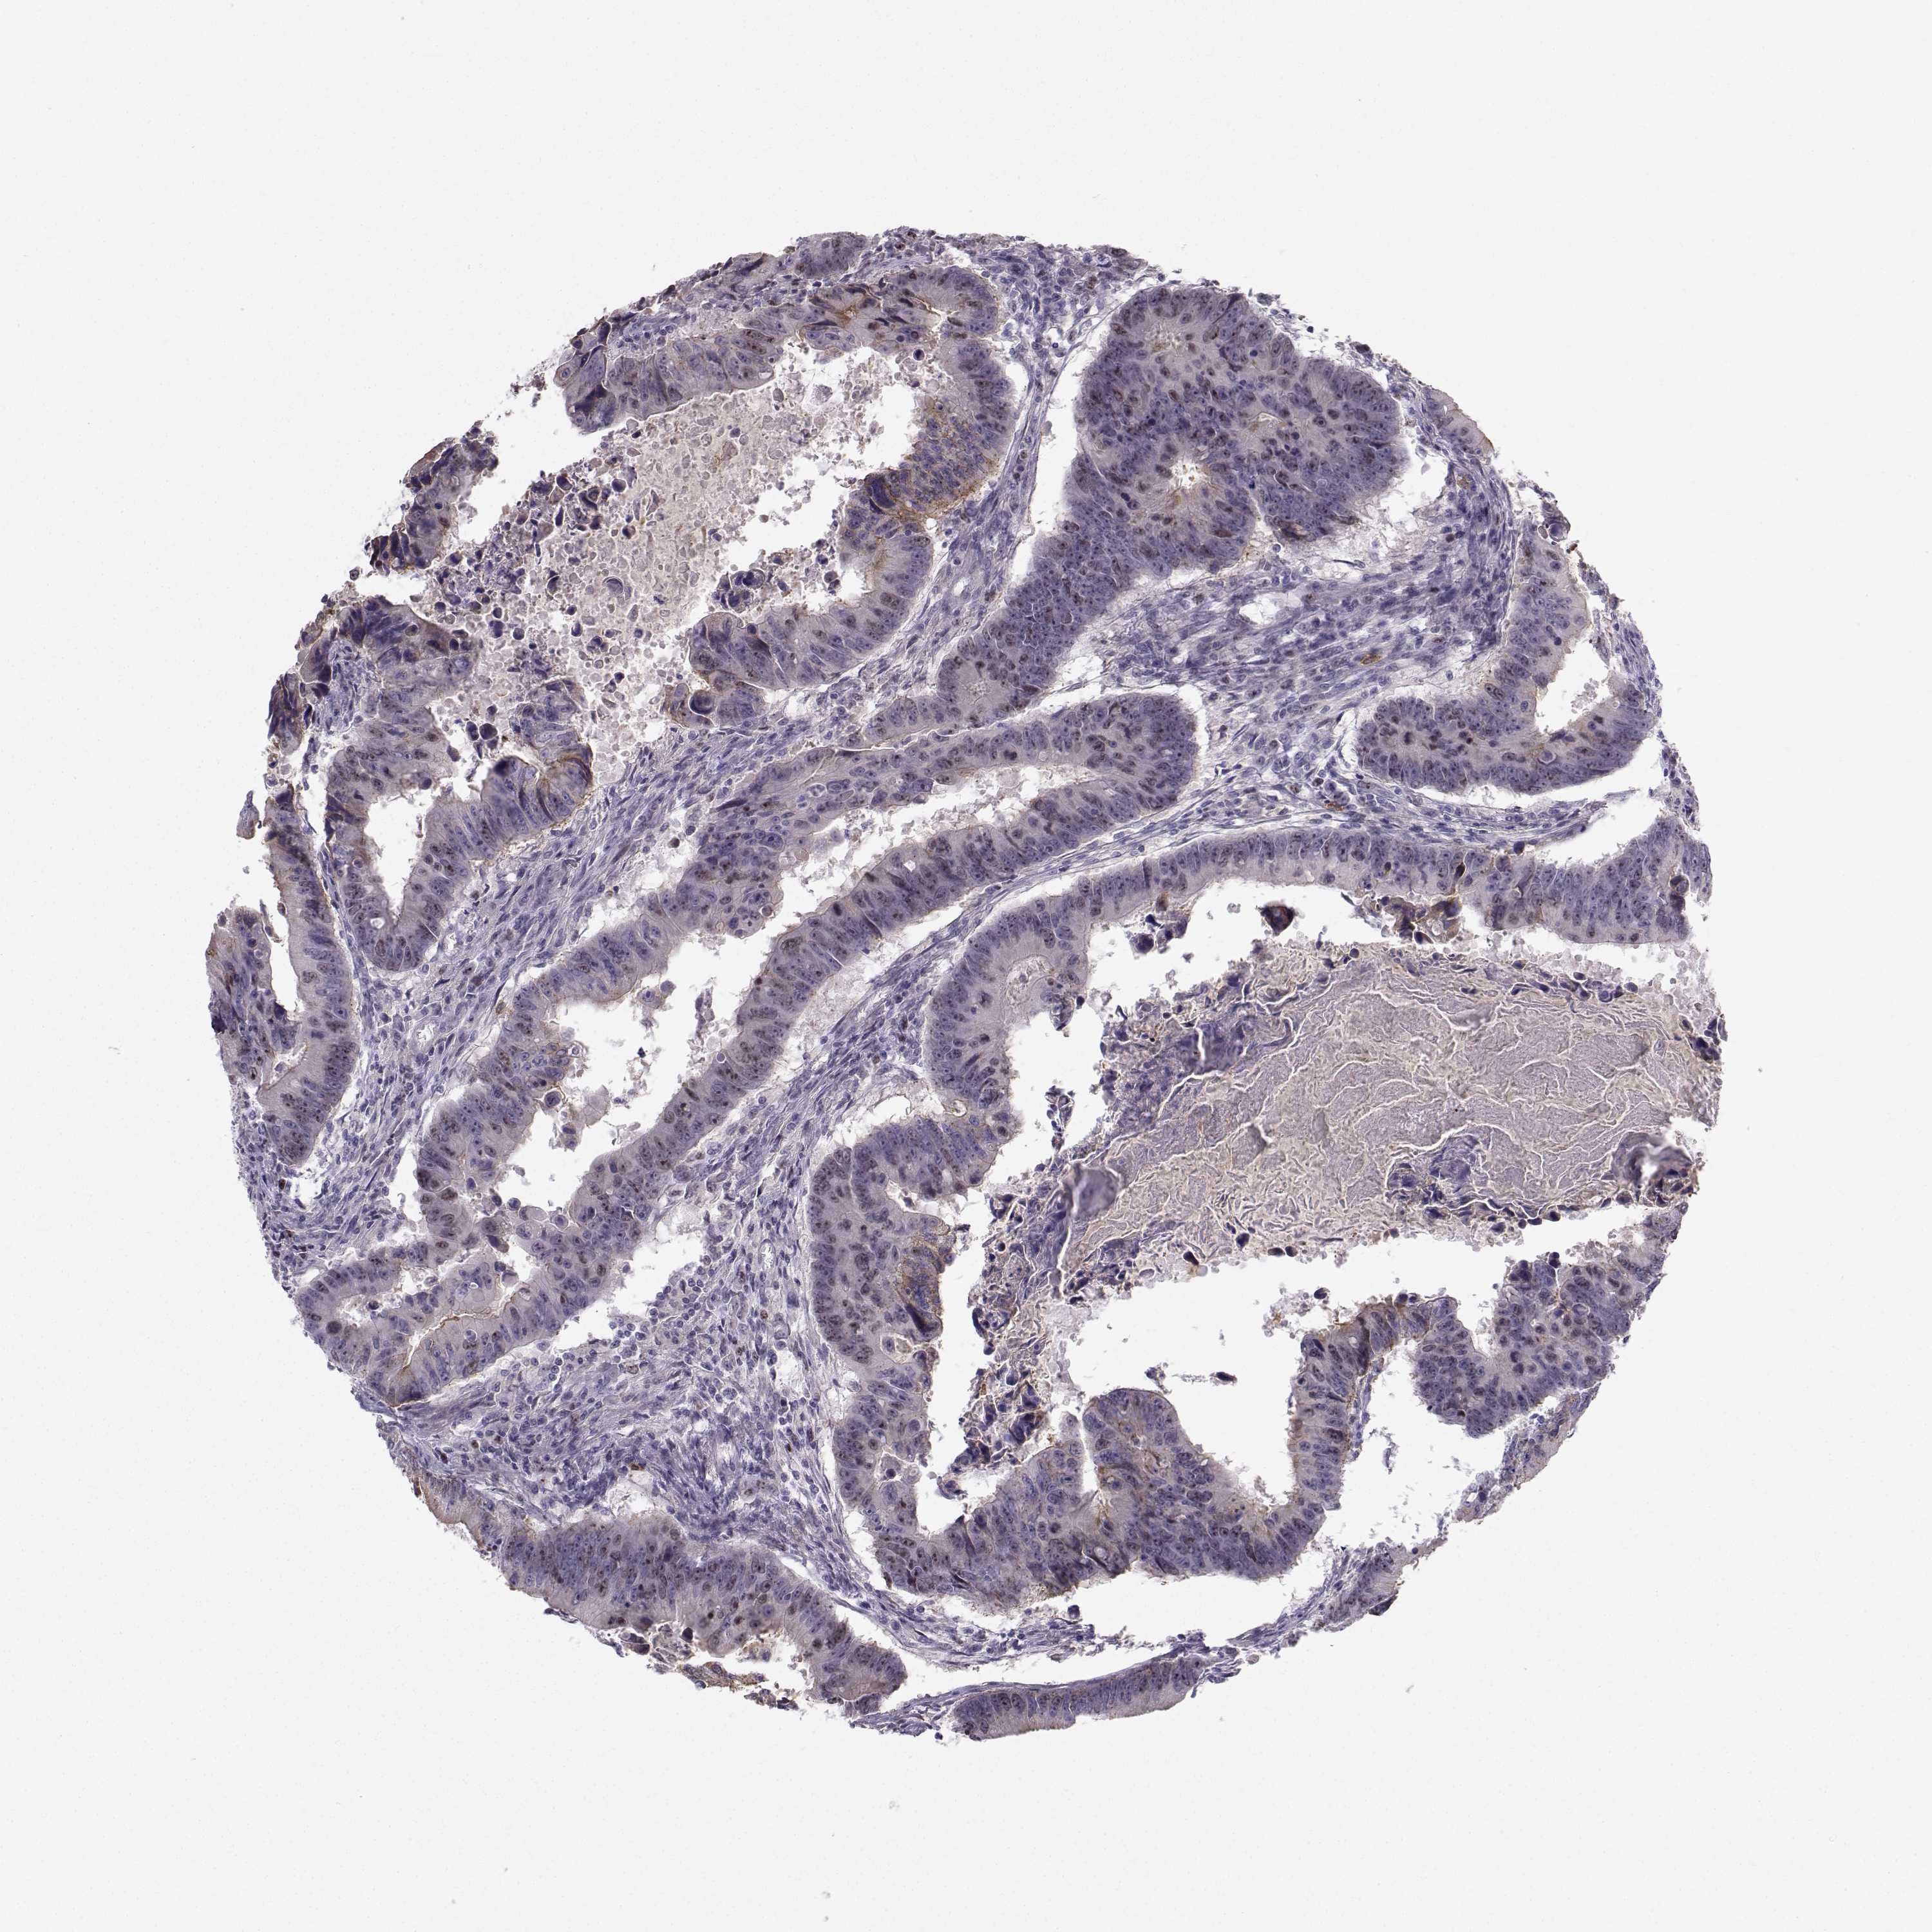

CANCER COLORECTAL CANCER Show tissue menu

Colorectal cancer

Human cancer

Colon adenocarcinoma